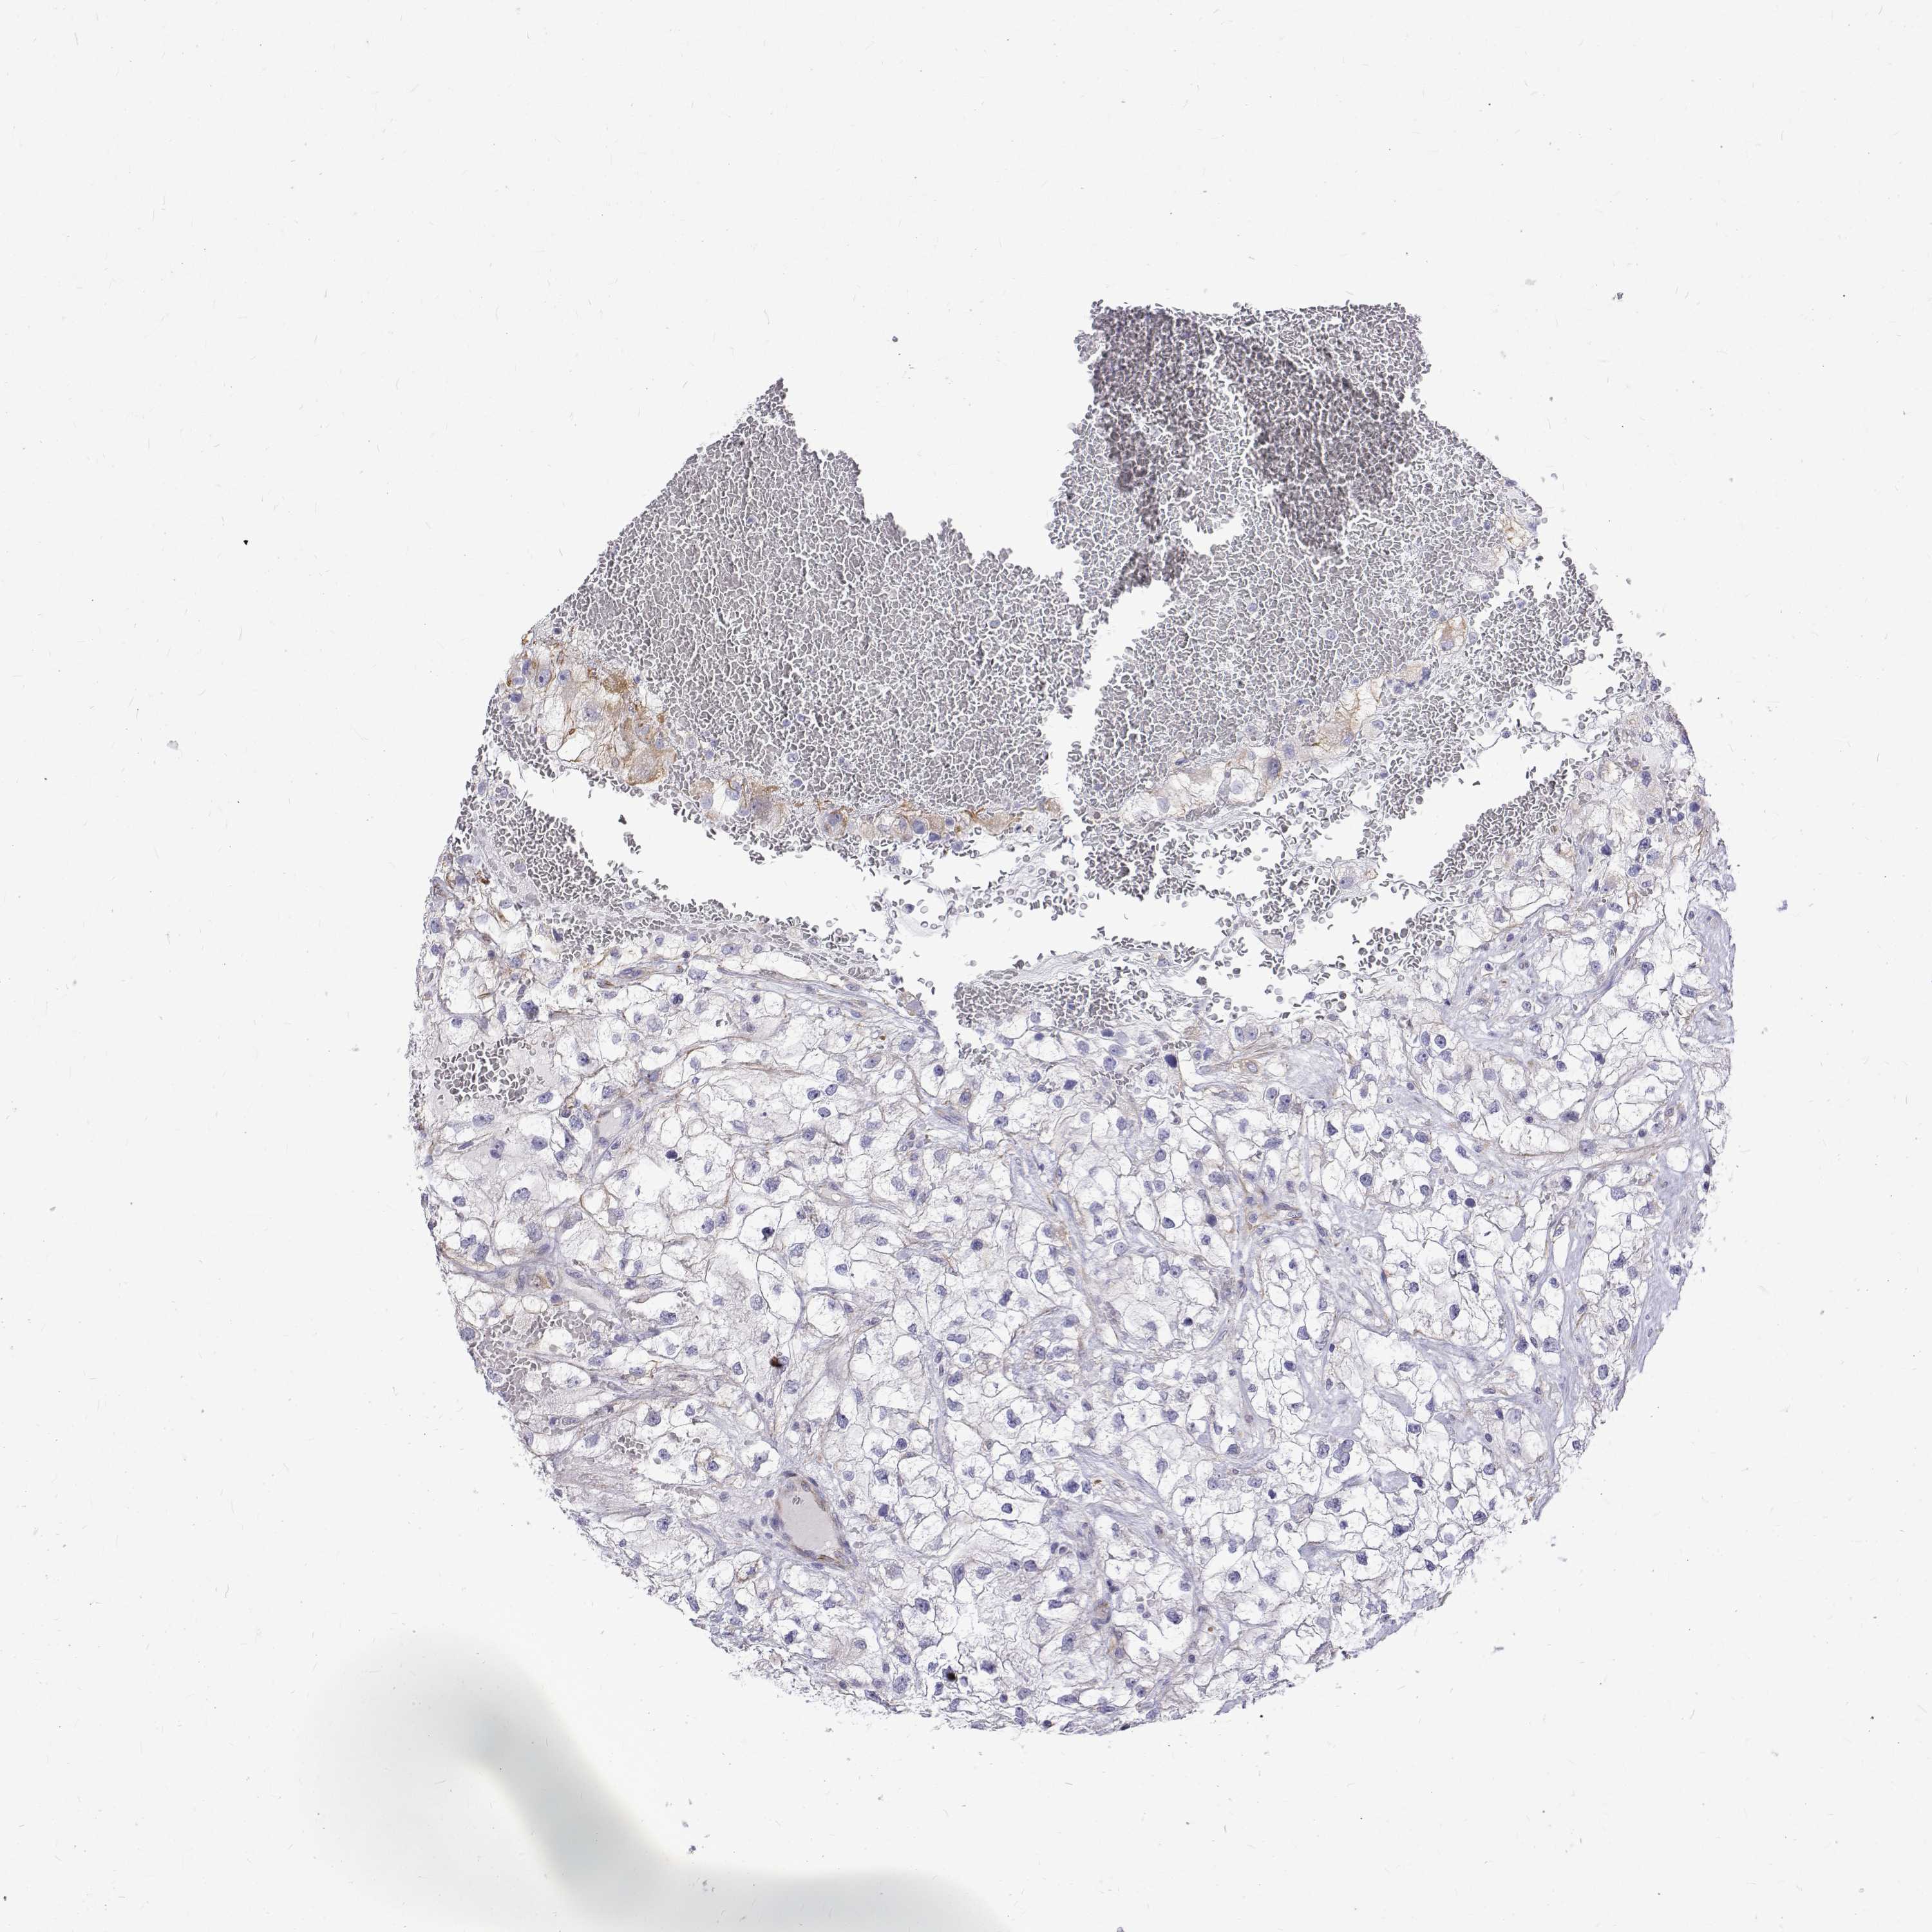

KIDNEY CHROMOPHOBE (TCGA) - Interactive survival scatter ploti

The Survival Scatter plot shows the clinical status (i.e. dead or alive) for all individuals in the patient cohort, based on the same data that underlies the corresponding Kaplan-Meier plots. Patients that are alive at last time for follow-up are shown in blue and patients who have died during the study are shown in red.

The x-axis shows the expression levels (FPKM) of the investigated gene in the tumor tissue at the time of diagnosis. The y-axis shows the follow-up time after diagnosis (years). Both axes are complimented with kernel density curves demonstrating the data density over the axes. The top density plot shows the expression levels (FPKM) distribution among dead (red) and alive patients (blue). The right density plot shows the data density of the survived years of dead patients with high and low expression levels respectively, stratified using the cutoff indicated by the vertical dashed line through the Survival Scatter plot. This cutoff is automatically defined based on the FPKM cutoff that minimizes the p-score. The cutoff can be changed by dragging the vertical line or by entering a cutoff value in the square labeled "Current cut-off".

Under the Survival Scatter plot the p-score landscape (black curve; left axis) is shown together with dead median separation (red curve; right axis). Dead median separation is the difference in median mRNA expression between patients who have died with high and low expression, respectively. It is calculated as follows: median FPKM expression of dead patients with high expression - median FPKM expression of dead patients with low expression. This is intended to aid the user in visually exploring custom cutoffs and the associated p-scores and dead median separation.

Individual patient data is displayed and can be filtered by clicking on one or more of the category buttons on the top of the page. Categories describing expression level and patient information include: high, low, alive, dead, female, male and tumor stages. The scale of the x-axis can be toggled between linear and log-scale by clicking on the "x log" button. Mouse-over function shows TCGA ID, patient information and mRNA expression (FPKM) for each patient.

& Survival analysisi

Kaplan-Meier plots summarize results from analysis of correlation between mRNA expression level and patient survival. Patients were divided based on level of expression into one of the two groups "low" (under cut off) or "high" (over cut off). X-axis shows time for survival (years) and y-axis shows the probability of survival, where 1.0 corresponds to 100 percent.

Survival analysis data not available.

TCGA RNA samplesi

RNA-seq data is reported as average FPKM (number Fragments Per Kilobase of exon per Million reads), generated by the The Cancer Genome Atlas (TCGA) .

Normal distribution across the dataset is visualized with box plots, shown as median and 25th and 75th percentiles. Points are displayed as outliers if they are above or below 1.5 times the interquartile range. FPKM values of the individual samples are presented next to the box plot.

Average pTPM 0.0

Number of samples 64